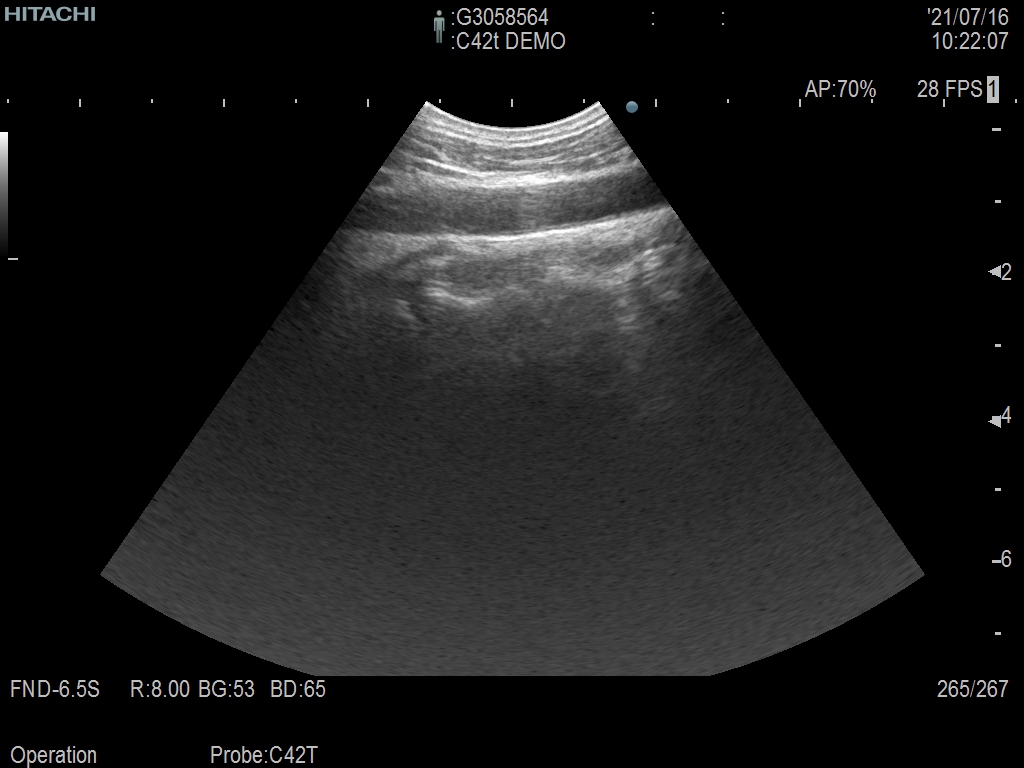

Hitachi C42T Ref Intraoperative Convex – ARIETTA

ARIETTA Convex C42T Intraoperative

Intraoperative Finger-grip T-Style

10 – 3 MHz

Hitachi C42T Intraoperative Convex – ARIETTA

Frequency Range: 10 – 3 MHz

Scan Width: 20 mm Radius

Scan Angle: 65° FOV

Hitachi C42T Intraoperative Convex – ARIETTA for Intraoperative Finger-grip Convex T-Style

| Ακτινολογικές λειτουργίες | Contrast Harmonic Imaging (CHI), Elastography (RTE), RT Sonography (RVS) |